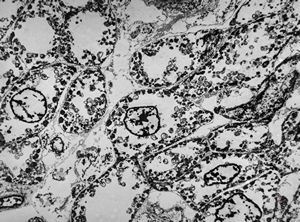

normal myocardium (N … nuclei of cardiomyocytes, K … capillaries)